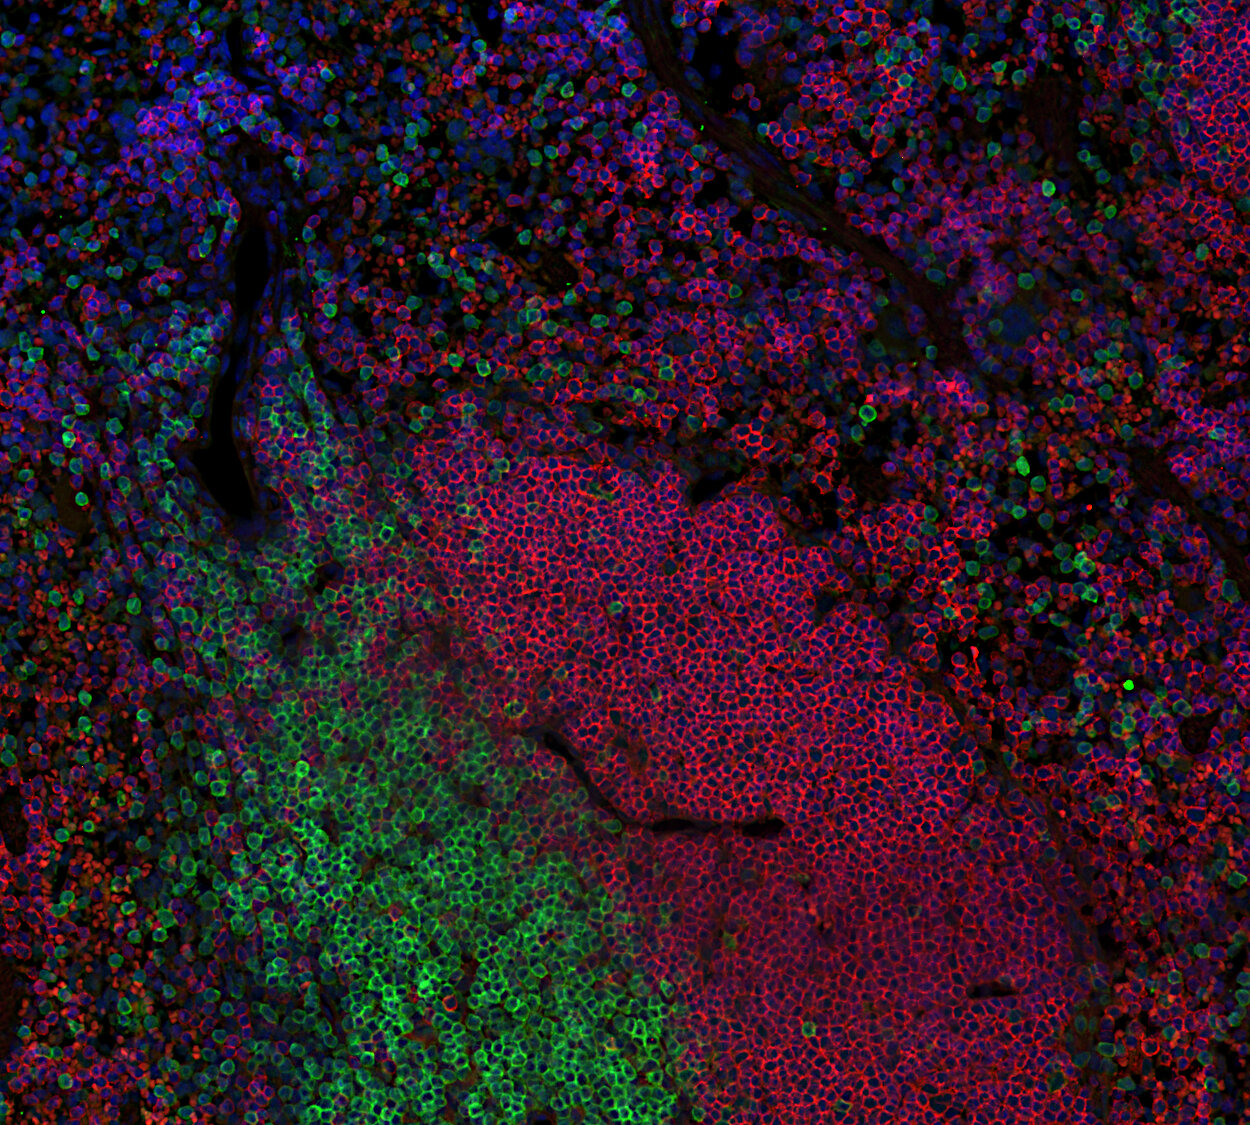

Fluorescent double staining for CD19 (red) and CD3e (green) visualizes B-cell and T-cell populations in the mouse spleen